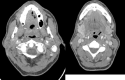

Case presentation: A 51-year-old male patient with human immunodeficiency virus and on highly active antiretroviral therapy (HAART) presented with a cT4aN2c SCCa of the tongue. He received a preoperative single course of Quad-Shot radiation therapy to 14 Gy in 4 fractions followed by surgical resection. Patient had no residual carcinoma on surgical pathology and no evidence of disease on subsequent clinical and radiological exams.